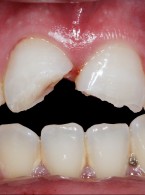

Postępowanie w utracie żywotności miazgi w zębach stałych niedojrzałych siecznych po urazie – opis dwóch przypadków

Zobacz więcej

Opublikowano dnia : 20.02.2025